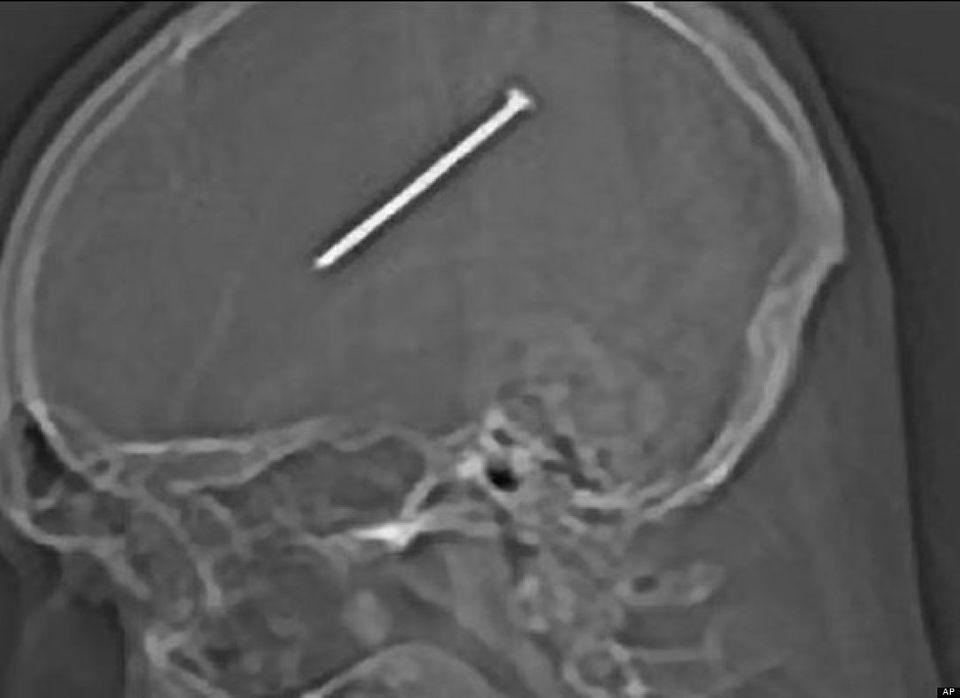

Bức ảnh chụp cắt lớp này được bệnh viện Miguel Couto công bố ngày 16/8/2012. Đây là trường hợp bệnh nhân 24 tuổi, là công nhân xây dựng và bị tai nạn thanh sắt từ trên cao rơi trúng đầu trong khi làm việc ở Rio de Janeiro (Brazil). Các bác sĩ cho biết bệnh nhân may mắn vì thanh sắt dài 15cm xuyên đúng giữa 2 chân mày qua sau đầu và các bác sĩ đã mất hơn 5 tiếng để lấy thanh sắt này ra.